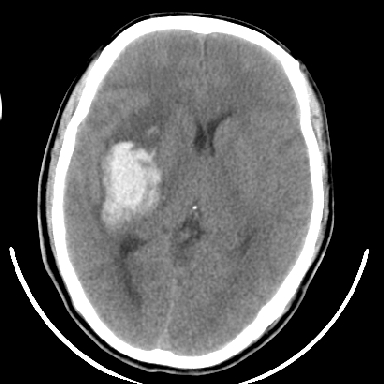

标题: CT6056:脑出血(血管畸形?) [打印本页]

标题: CT6056:脑出血(血管畸形?)

m 40突发头痛左侧偏瘫3小时

考虑高血压性脑出血,依据:

1是高血压性脑出血的好发部位,形态呈肾形,是高血压性脑出血的常见形状

2增强时占位效应加重了,考虑出血还没有停止

3病灶周围水肿不是太厉害,一般肿瘤出血水肿多非常明显

4病灶周围的‘软组织’影没有明显的强化

5至于脑血管畸形引起的出血,暂时没有看到明显的畸形血管影,也不太支持

支持右侧基底节脑出血

右侧基底节区脑出血.

支持右侧基底节区(主要为外囊区)原发性脑出血。

另附部分资料:“血液溢出血管外形成血肿,其内含有大量血红蛋白、血浆白蛋白,球蛋白,因这些蛋白对x线的吸收系数高于脑质,故ct呈现高密度阴影,ct值达40~90h,最初高密度灶呈非均匀一致性,中心密度更高,新鲜出血灶边缘不清。基底节区血肿多为“肾”型,内侧凹陷,外侧膨隆,因外侧裂阻力较小,故向外凸,其它部位血肿多呈尖圆形或不规则形”

术中抽出40ml陈旧血液,血肿底部似见一条索血管影